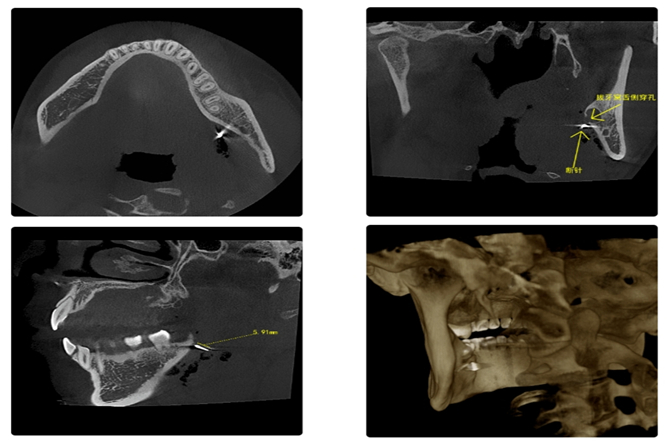

術(shù)前CBCT考慮到小帥拔除阻生智齒時(shí)張口時(shí)間較長(zhǎng),再次手術(shù)取斷針局麻配合較差,為最大程度一次性取針成功,口腔科采用全身麻醉方式,避開(kāi)因患者張口困難、局部疼痛等因素。

手術(shù)前,反復(fù)對(duì)比CBCT及口內(nèi)情況,準(zhǔn)確判斷斷針的位置。

口腔醫(yī)生從舌側(cè)切口入路,行粘骨膜翻瓣,通過(guò)牙槽窩穿孔部位,大致鎖定斷針于口內(nèi)空間方位,小心分離,充分保護(hù)舌神經(jīng),向內(nèi)、下方探查,最終確認(rèn)斷針嵌頓于下頜舌骨肌中。然后選擇相應(yīng)器械尋找并取出斷針,長(zhǎng)約6mm。取出斷針后,生理鹽水反復(fù)沖洗創(chuàng)口,拉攏粘骨膜瓣,間斷對(duì)位縫合,紗布?jí)浩戎寡?。術(shù)后恢復(fù)良好,無(wú)明顯舌體麻木癥狀。